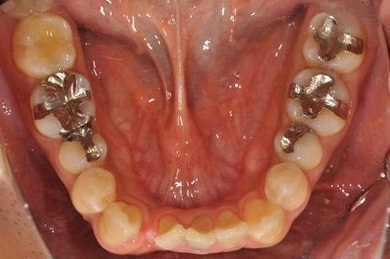

| 性別/年齢 | 男性 / 36歳 | ||||||||||||||||||||||||||||||||

| 主訴 | 事故で欠損した上部の歯4本、下1本のインプラント治療相談。 | ||||||||||||||||||||||||||||||||

| 治療内容 | インプラント2本(GBR、自家骨移植)、メタルボンドセラミック4本、結合組織移植術 | ||||||||||||||||||||||||||||||||

| 総治療費 | 1,766,520円 | ||||||||||||||||||||||||||||||||

| 治療期間 | 1年8ヶ月 |